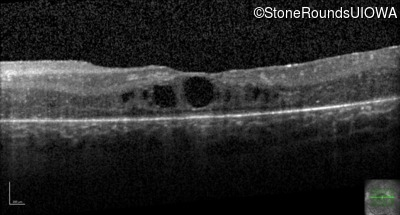

Age at visit: 17 years

This 17 year old female feels that the vision in her right eye has worsened since her cataract surgery 8 weeks ago.